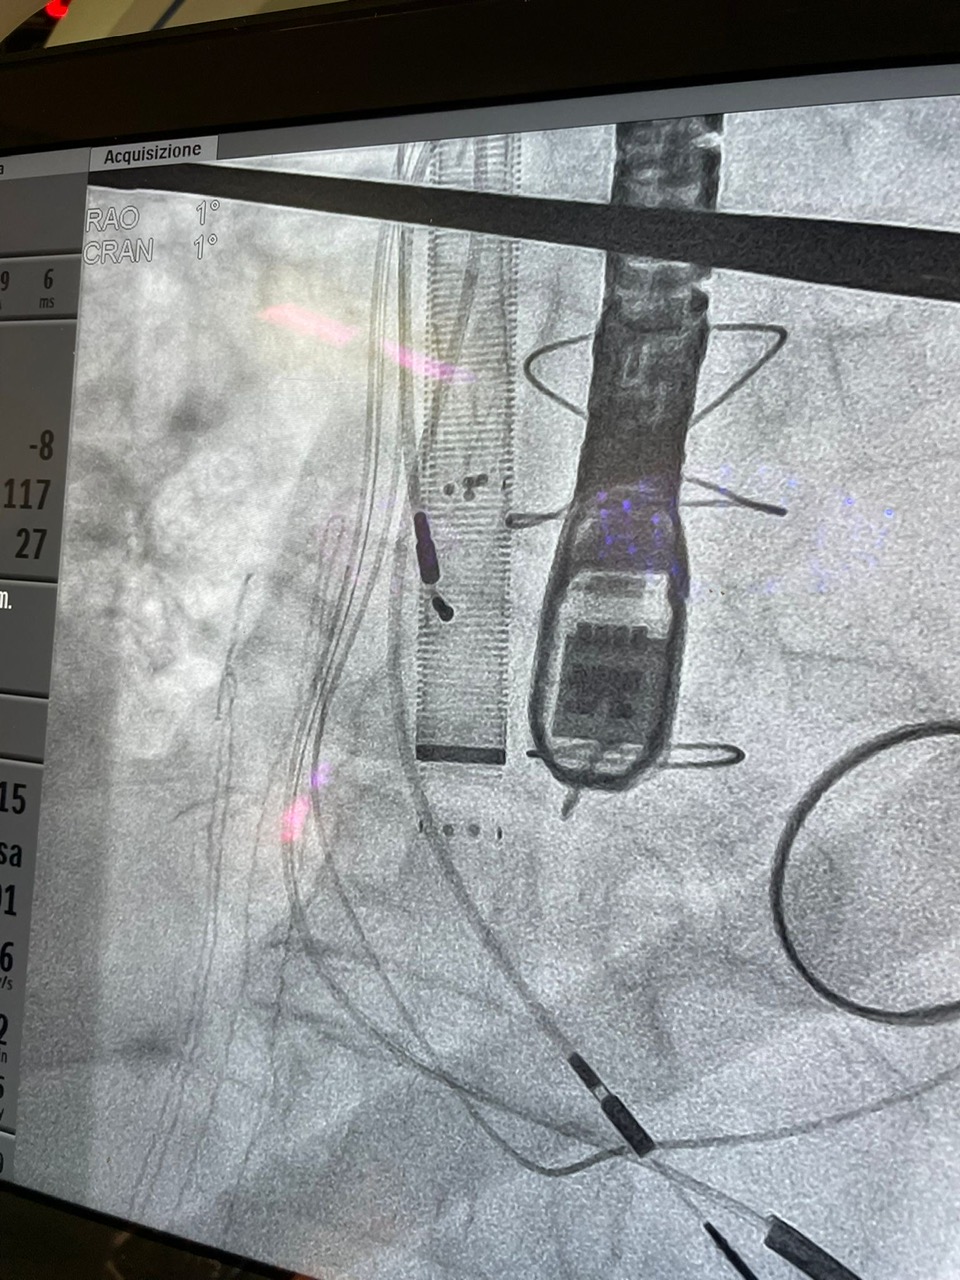

Un delicato intervento con l’utilizzo della procedura al suo debutto, in particolare, è stato eseguito in una delle moderne sale operatorie del presidio “Rodolico” di via Santa Sofia, per l’asportazione di una grossa “vegetazione fungina endocardiaca dalla valvola tricuspide”, vale a dire una serie di trombi formatisi nell’atrio destro del cuore di una donna settantenne, a seguito dell’infezione di cavi legati al pace maker per l’elettrostimolazione cardiaca.

La metodica AngioVac, estremamente mininvasiva, in questo caso ha incluso una cannula di aspirazione, inserita da una vena giugulare, dotata alla sua estremità di una struttura espandibile a forma di ventaglio così da poter catturare e aspirare agilmente la massa fungina.